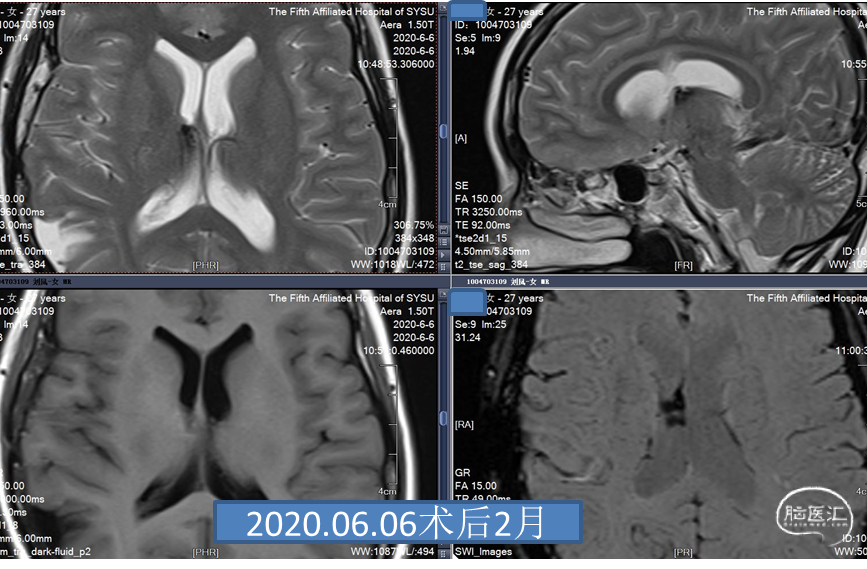

患者,女,27岁,发现脑室旁海绵窦状血管瘤,是一种多发的海绵状血管瘤。反复出血两次,用显微镜手术。9天后复查,可见一定血丝,2个月后复查,很干净,病人无明显病灶。今年复查见对侧丘脑有一血肿,手术难度大。